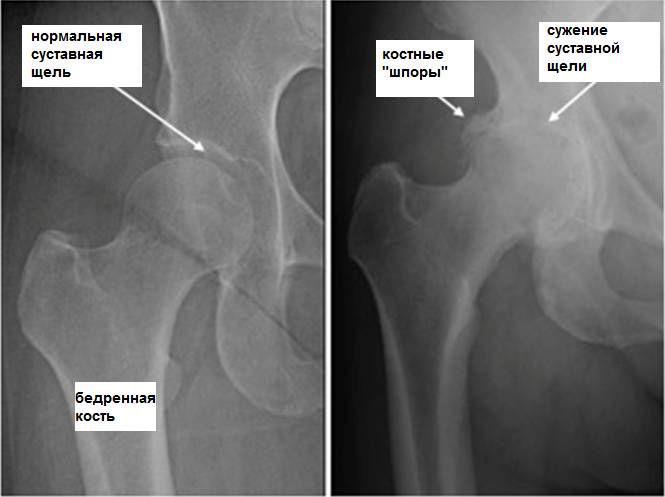

Коксартроз

Причиной развития такого заболевания является изменения структуры хрящевой ткани, нарушение питания и кровоснабжения тканей. Спровоцировать проблему может аномальное строение скелета, нарушение обменных процессов в организме, слишком большая масса тела. Симптоматика при этом такова: изначально появляется стартовая боль, которая имеет умеренную интенсивность. Однако со временем дискомфорт и неприятные ощущения усиливаются.

Если на 1 стадии сначала они появляются только при движении, то с развитием заболевания болевой синдром не проходит даже во время покоя. На второй и третьей стадиях развития патологии боль не исчезает даже ночью. Объем движения уменьшается с каждым днем. Естественно, необходимо обязательно проводить лечение этой болезни. Если она уже запущена, то на 4 стадии патологии придется делать операцию. Дело в том, что болезнь способствует деформации тазобедренного сустава. При данном заболевании болевые ощущения могут появляться даже в боку, паху и колене. Мышцы при коксартрозе сильно напрягаются, больной начинает хромать.